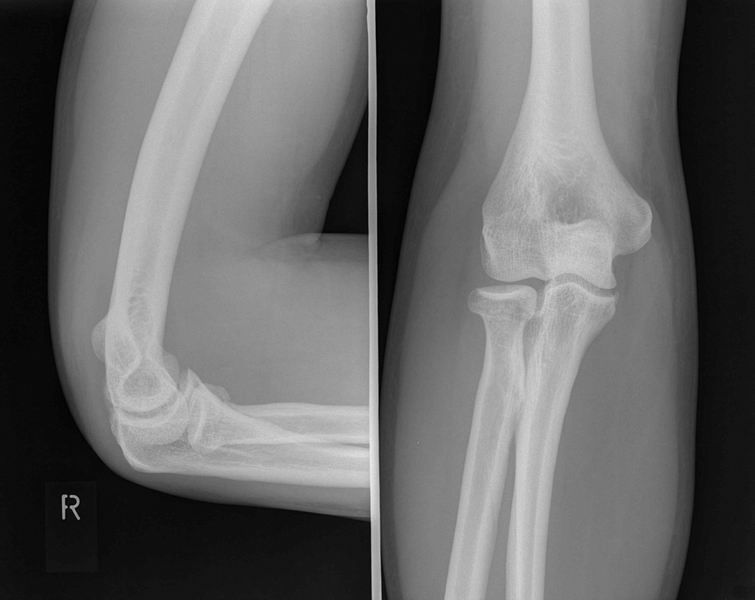

Elleboog